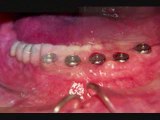

Deland Implant Dentistry- Expert Dentist Near Dentist Lady Lake, Eustis, Mount Dora, The Villages, Tavares, Fruitland Park. For more information please visit : http://www.delandimplants.com/dentisteustis-mountdora.htm